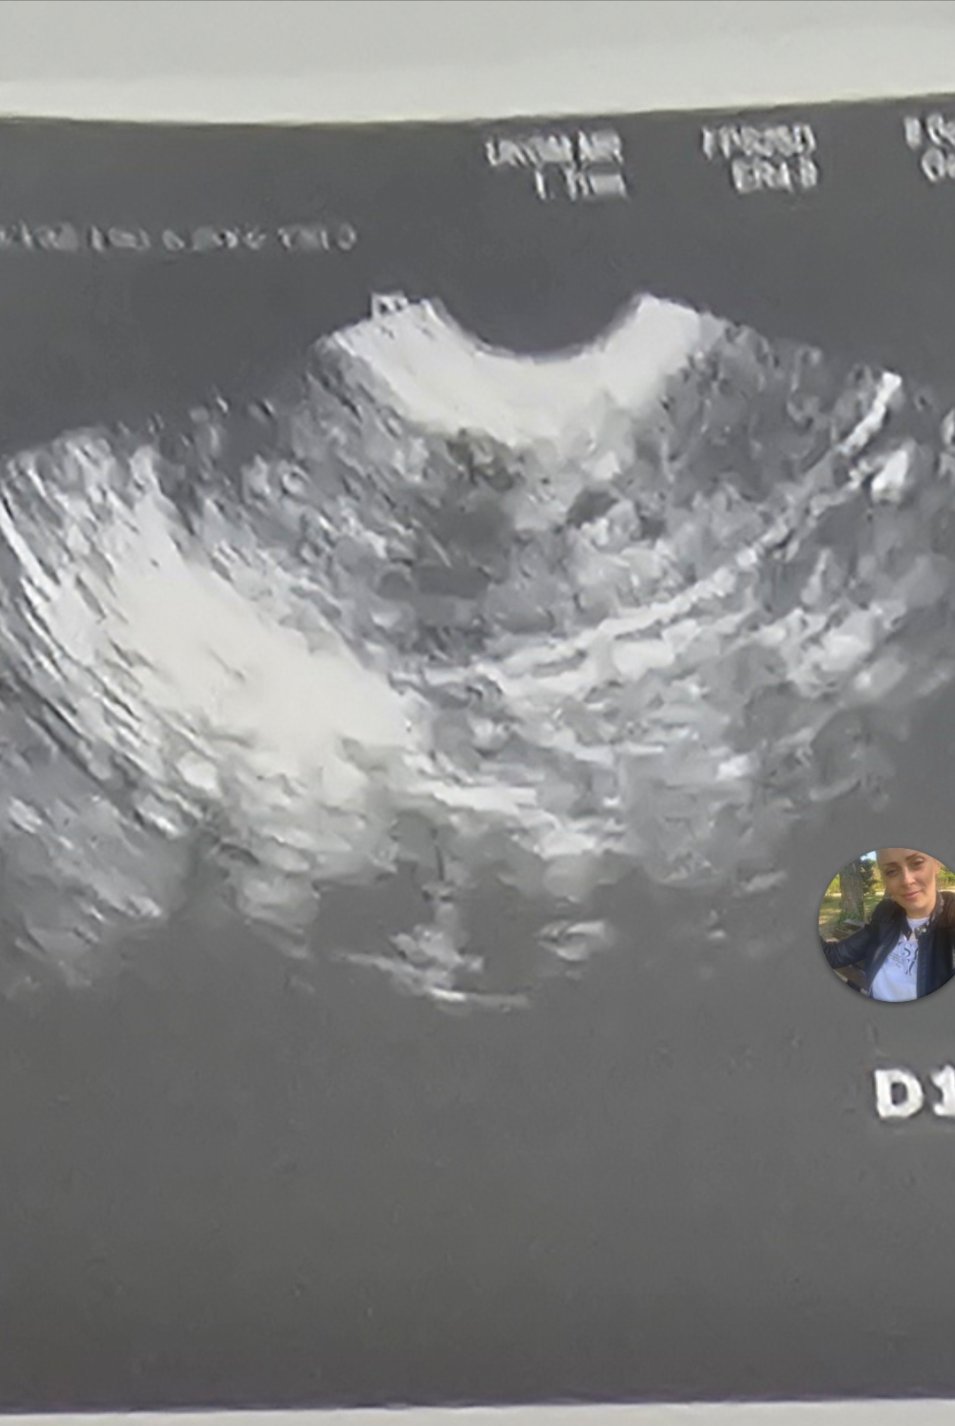

Ехографска снимка

Лекарят каза, че или е киста или жълто тяло... Каза след М.Ц. Да отида отново. А прегледа го прави с вътрешен видеозон. Не съм компетентна и за това питам тук

Еми той ти го е казал. За мен е доста голямо и според мен е киста, която  може да се оправи  и сама.

Виж по снимката, трябва да има замерени големината (...Яйчникът на полово зрялата жена има форма и големина на бадем (дължина 3 – 4 см, ширина 2 – 2,5 см)...). Не се вижда хубаво от снимката.

Здравейте, момичета! Някой може ли да ми помогне с разчитането на снимката?